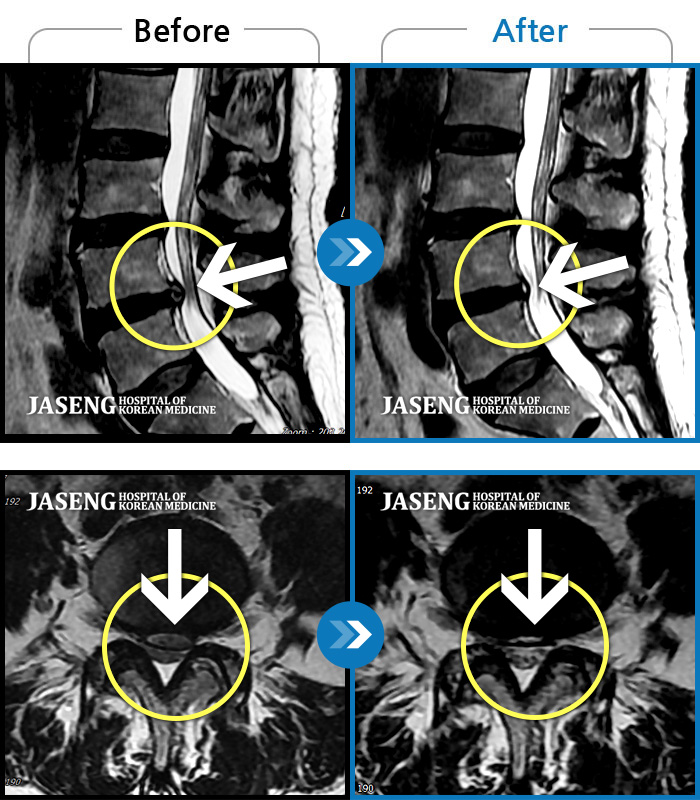

허리디스크

목동 · 고웅 원장

허리통증으로 보행 불가. 우측 다리의 통증과 저림, 화끈거리는 통증과 차가운 느낌 번갈아 나타남

촬영시기

2020.12.18 ~ 2024.11.15

2024.12.24